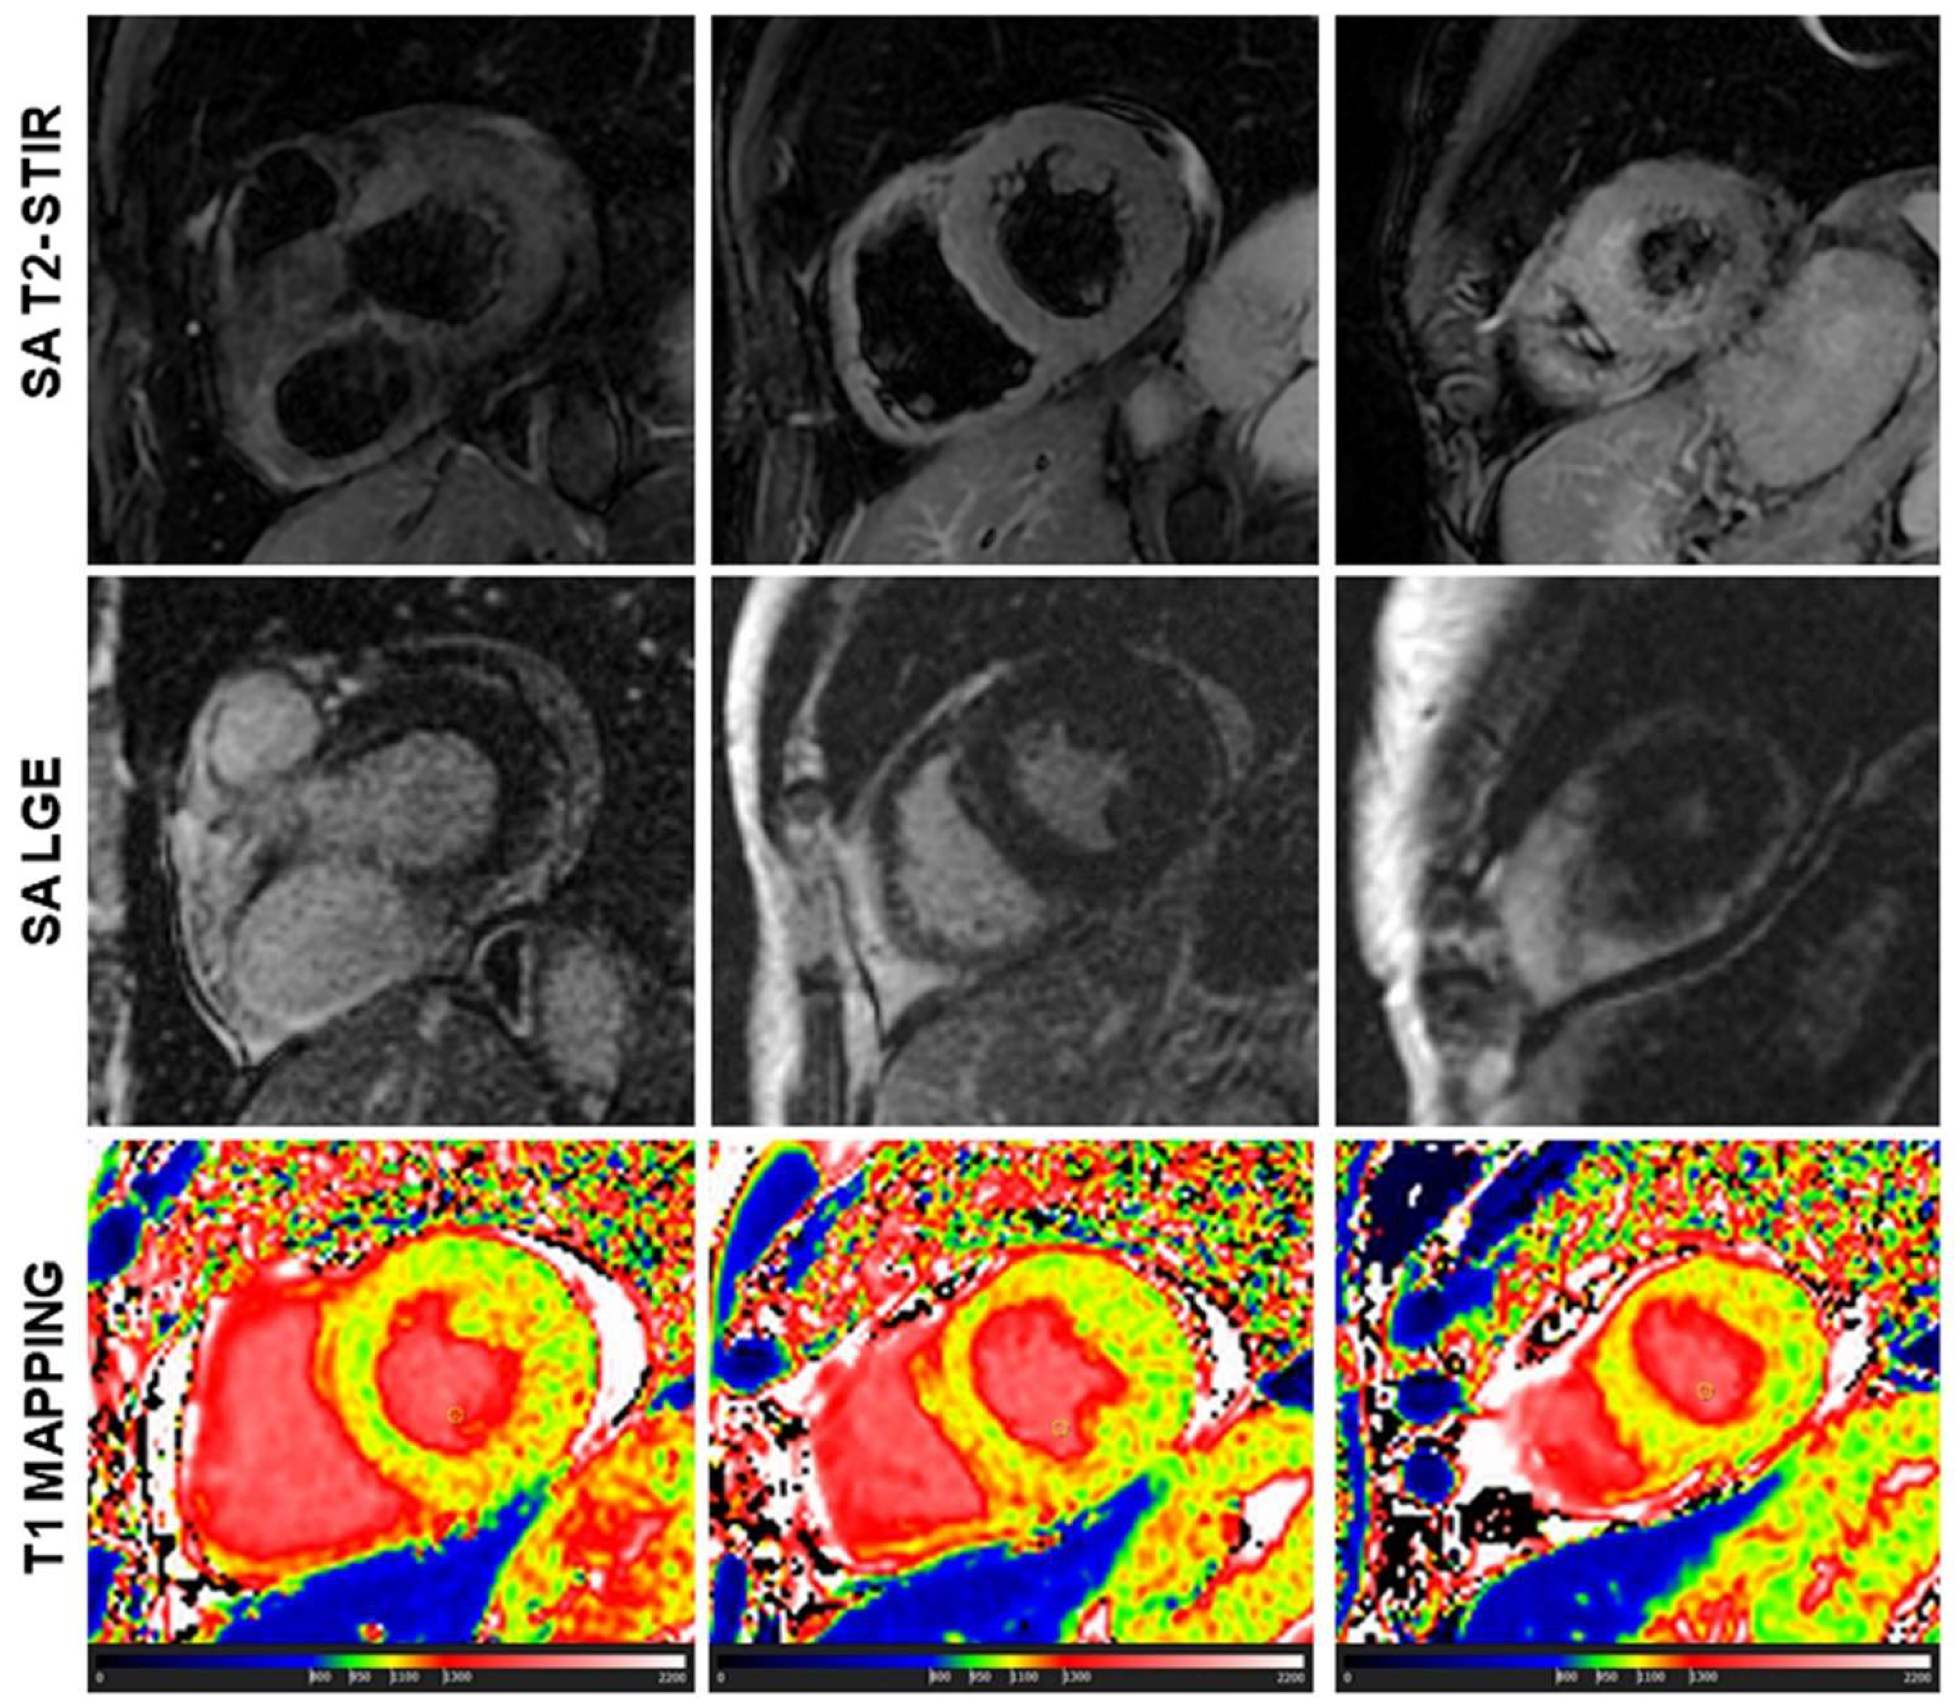

3.1. Conventional CMR vs. T1 Mapping

3.2. Diagnostic Role of T1 Mapping

3.3. Diffuse vs. Regional Myocardial Damage